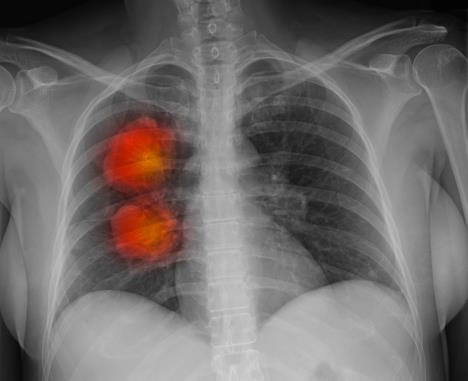

Direktorka Klinike za pulmologiju KCS prof. Violeta Vučinić Mihailović kaže da se u toj zdravstvenoj ustanovi godišnje zbrine više od 5.000 pacijenata, a da skoro svaki treći dođe sa uznapredovalom formom karcinoma pluća.

- Samo u ovoj klinici prošle godine umrlo je 200 pacijenata, što je mnogo. Kod najvećeg broja pacijenata bolest se otkrije u kasnom stadijumu, kada je primena terapije dovedena u pitanje, rekla je Vučinić Mihailović na konferenciji povodom Svetskog dana borbe protiv raka pluća.

Bolest se obično otkriva u kasnoj fazi, jer je podmukla, pacijent obično nema tegobe, a kada se one jave obično je već uznapredovala.

- To je najčešće dijagnostikovan rak kod muškaraca i karakteriše ga visoka stopa smrtnosti. Pošto se otkriva kasno period preživljavanja od dijagnostike do smrtnog ishoda kratak, rekla je Jovanović.

Predstavnik Svetske zdravstvene organizacije (SZO) u Srbiji Aleksandar Bojović ukazao je da je u svetu prošle godine registrovano 2,09 miliona novoobolelih od karcinoma pluća, a da je u toj godini umrlo 1,76 miliona pacijenata.